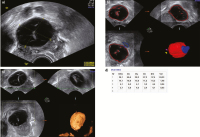

Abbildung 3a-d: 11. Zyklustag bei Low-dose-Stimulation: (a) Zunächst wird der Follikel in der maximalen Größe dargestellt und gemessen, (b) in der Folge wird der Schallkopf 90° gedreht und eine weitere Messung durchgeführt. (c) Die Sono-AVC-Messung zeigt den größten Follikel in Rot an. (d) Die Messung zeigt zuerst den auf die elliptische Form des Follikels bezogenen Follikeldurchmesser D(V), dann die Messung in 3 Ebenen, wie sie das System vornimmt, und dann den Mittelwert aus Dx, Dy und Dz. Der letzte Wert gibt das errechnete Volumen in Millilitern an.

Abbildung 4a-d: 14. Zyklustag bei Clomifen-Stimulation: (a) Zunächst wird der Follikel in der maximalen Größe dargestellt und gemessen, (b) in der Folge wird der Schallkopf 90° gedreht und eine weitere Messung durchgeführt. (c) Die Sono-AVC-Messung zeigt den größten Follikel in Rot an. (d) Die Messung zeigt zuerst den auf die elliptische Form des Follikels bezogenen Follikeldurchmesser D(V), dann die Messung in 3 Ebenen, wie sie das System vornimmt, und dann den Mittelwert aus Dx, Dy und Dz. Der letzte Wert gibt das errechnete Volumen in Millilitern an.